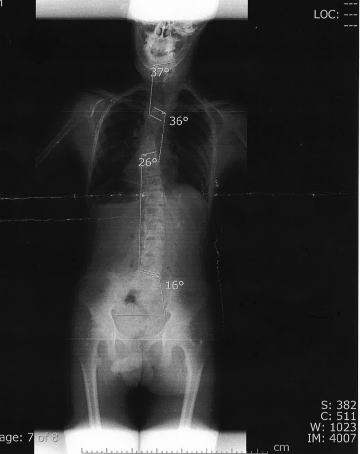

Hの半年に1度の整形に。

![]() | やはり徐々に曲りが強くなっている。 |

痛みがでなければいいのだけれど・・・。

このまま成長期が終わればセーフ、でももう少し伸びて欲しい・・・。